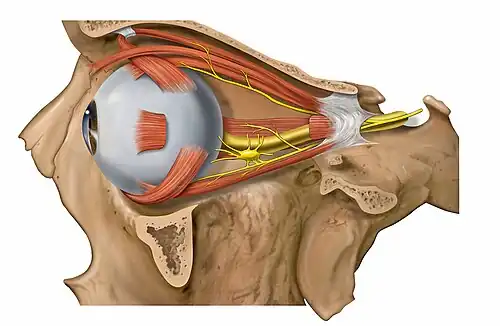

Diagram of human eye with surrounding superior, oblique, medial and inferior rectus muscles; supraorbital foramen shown above the eye, and inferior orbital fissure inferolaterally. | |

Eye movement

The movement of the eye is controlled by extraocular muscles; in humans, the six distinct muscles are the superior, an inferior, a medial and a lateral rectus, as well as a superior and an inferior oblique. The superior ophthalmic vein is a sigmoidal vessel along the superior margin of the orbital canal that drains deoxygenated blood from surrounding musculature. The ophthalmic artery is a crucial structure in the orbit, as it is often the only source of collateral blood to the brain in cases of large internal carotid infarcts, as it is a collateral pathway to the circle of Willis. In addition, there is the optic canal, which contains the optic nerve, or cranial nerve II, and is formed entirely by the lesser wing of the sphenoid, separated from the supraorbital fissure by the optic strut. Injury to any one of these structures by infection, trauma or neoplasm can cause temporary or permanent visual dysfunction, and even blindness if not promptly corrected.[10] The orbits also protect the eye from mechanical injury.[5]

Dissection showing origins of right ocular muscles, and nerves entering by the superior orbital fissure

Dissection showing origins of right ocular muscles, and nerves entering by the superior orbital fissure -